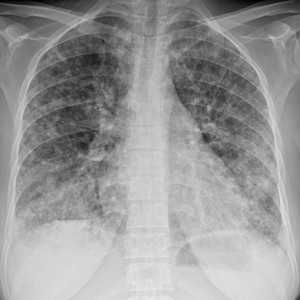

Метастазы в легких — фото рентгенограммы. Округлые тени — метастазы рака пищевода. Хорошо виден большой узел округлой формы вблизи переднего отрезка 2-го ребра. На снимке справа - циркулярное сужение пищевода за счет опухолевого утолщения его слизистой оболочки.

Как выглядят метастазы в легких на рентгене? Слева — узловые образования у пациента с раком яичка. Справа - метастазы рака яичников гематогенного характера с выраженным опухолевым лимфангиитом (обратите внимание на деформированный сетчатый, линейный характер легочного рисунка).